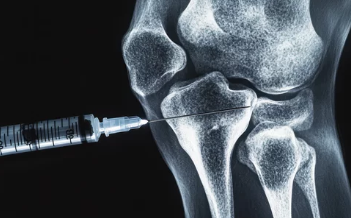

- 급성 발작 치료: 비스테로이드성 소염진통제(NSAIDs), 콜히친(Colchicine), 스테로이드 주사를 통해 염증과 통증을 완화합니다.

(4) 수술적 치료

- 통풍결절이 심하거나 관절 손상이 진행된 경우, 수술을 통해 제거하거나 관절을 교정할 수 있습니다.